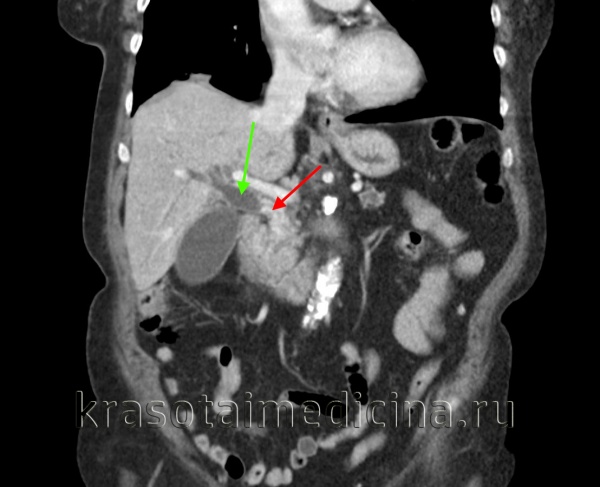

(Слева) На аксиальной КТ с контрастным усилением определяется выраженное неравномерное утолщение стенки желчного пузыря, непосредственная инвазия печени, а также перипанкреатическая/портокавальная и забрюшинная лимфаденопатия. Увеличение лимфатических узлов этих групп является типичным проявлением рака желчного пузыря.

(Справа) На аксиальной КТ с контрастным усилением визуализируется большое гиподенсное образование в печени. Это образование может быть опухолью печени, однако желчный камень в его центре и невозможность визуализации желчного пузыря позволяют предположить, что образование представляет собой рак желчного пузыря с инвазией печени.

КТ ОБП. Внутрипротоковая холангиокарцинома (опухоль Клацкина) холедоха (красная стрелка). Расширенный холедох (зеленая стрелка). Расширенный главный панкреатический проток (желтая стрелка).

КТ ОБП (этот же пациент). Опухоль Клацкина холедоха (красная стрелка). Расширенный просвет холедоха до зоны обструкции (зеленая стрелка).